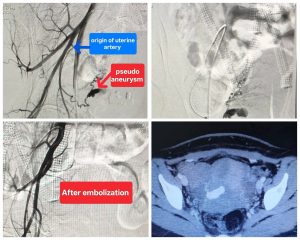

كان مستشفى صحة المرأة برئاسة الدكتور أحمد إبراهيم، قد استقبل سيدة تبلغ من العمر (٢٦) عاما، كانت تعاني من نزيف رحمي حاد أدى إلى هبوط حاد في الدورة الدموية، وذلك بعد مرور شهر على خضوعها لعملية ولادة قيصرية، وفور استقبال الحالة، تبين وجود نزيف مهبلي عنيف متكرر أدي لاضطراب العلامات الحيوية وتهديد حياة المريضة وبعد عمل أشعة مقطعية بالصبغة علي شرايين البطن والحوض تبين وجود ناسور شرياني وريدي وكيس دموي بالرحم، ليتم تحويل المريضة إلى قسم الأشعة التشخيصية والتدخلية بالمستشفى الرئيسي، وعلى الفور قام الفريق الطبي بإجراء تدخل دقيق باستخدام تقنيات الأشعة التدخلية لغلق الناسور والكيس الدموي بنجاح تام في وقت قياسي ودون أي مضاعفات تذكر.

تدخل الفريق الطبي من قسم الأشعة التشخيصية والتدخلية والتصوير الطبي بقيادة الدكتور حمدي محمد إبراهيم، أستاذ مساعد الأشعة التدخلية، يعاونه الدكتور إبراهيم أيمن، استشاري الأشعة، تحت إشراف الدكتور مصطفى الشرقاوي، أستاذ الأشعة التدخلية ورئيس الفريق النوبتجي.